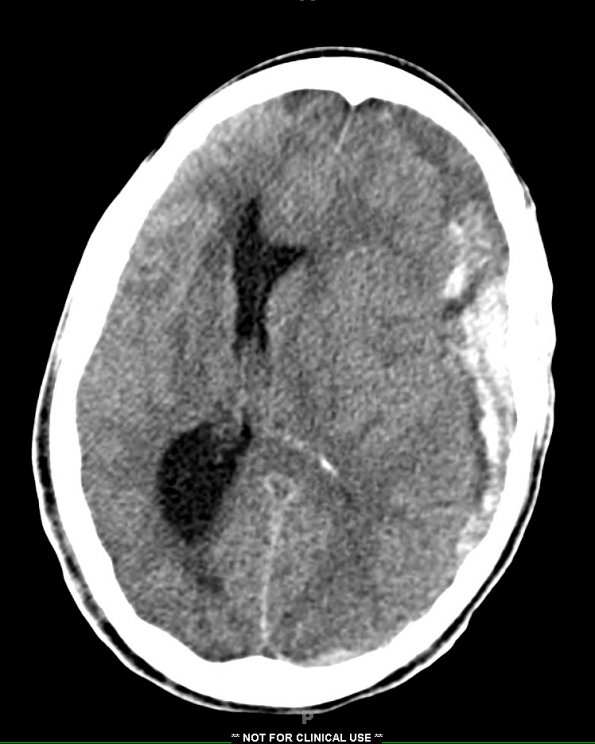

A large left subdural hemorrhage was found on CT examination.